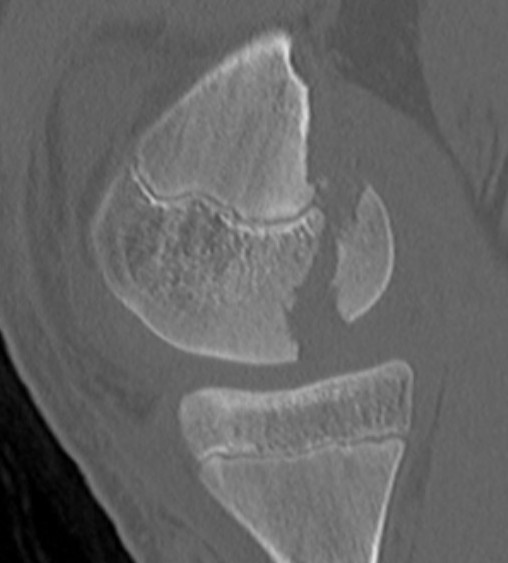

Definition

Hoffa Fracture Xray

Coronal plane fracture of distal femoral condyle

- intra-articular

- often only attachment is posterior capsule

CT

Aids surgical planning

Medial Hoffa CT 1Medial Hoffa CT 2Medial Hoffa CT 3Medial Hoffa CT 4